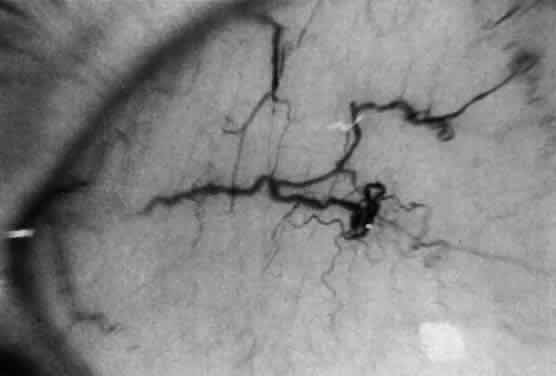

Corneal clouding (Fig. 10), hyperopic astigmatism, and a mild retinopathy with surface-wrinkling maculopathy (Fig. 11) appear to be the constant ocular triad.75 Some patients have retinal vascular tortuosity, optic nerve head swelling (Fig. 12), visual field defects, and abnormalities in color vision. Visual complaints are uncommon.

Fig. 12. Optic nerve head swelling in a patient with mucolipidosis III. (Traboulsi E, Maumenee I: Ophthalmologic findings in mucolipidosis III. Am J Ophthalmol 102:529, 1986)